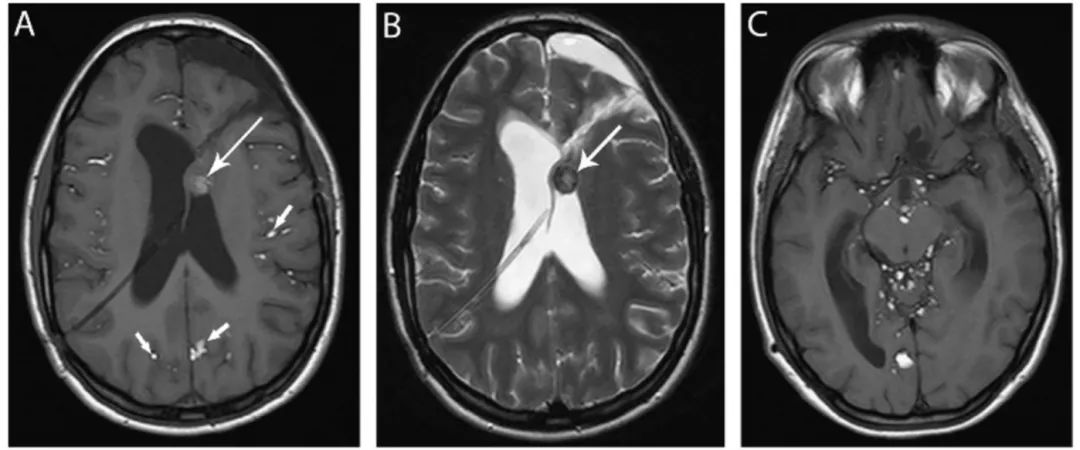

图15 皮样囊肿

(A) 轴位T1WI像显示侧脑室内已部分切除的多发高强度病灶(长箭头),蛛网膜下腔内散在T1高信号病灶(短箭头),可能为皮样囊肿破裂的溢出物。(B)轴位T2WI像显示囊肿内混合高低信号(箭头)。(C)轴位T1WI像显示更多高强度病灶,为囊肿内容物溢出。